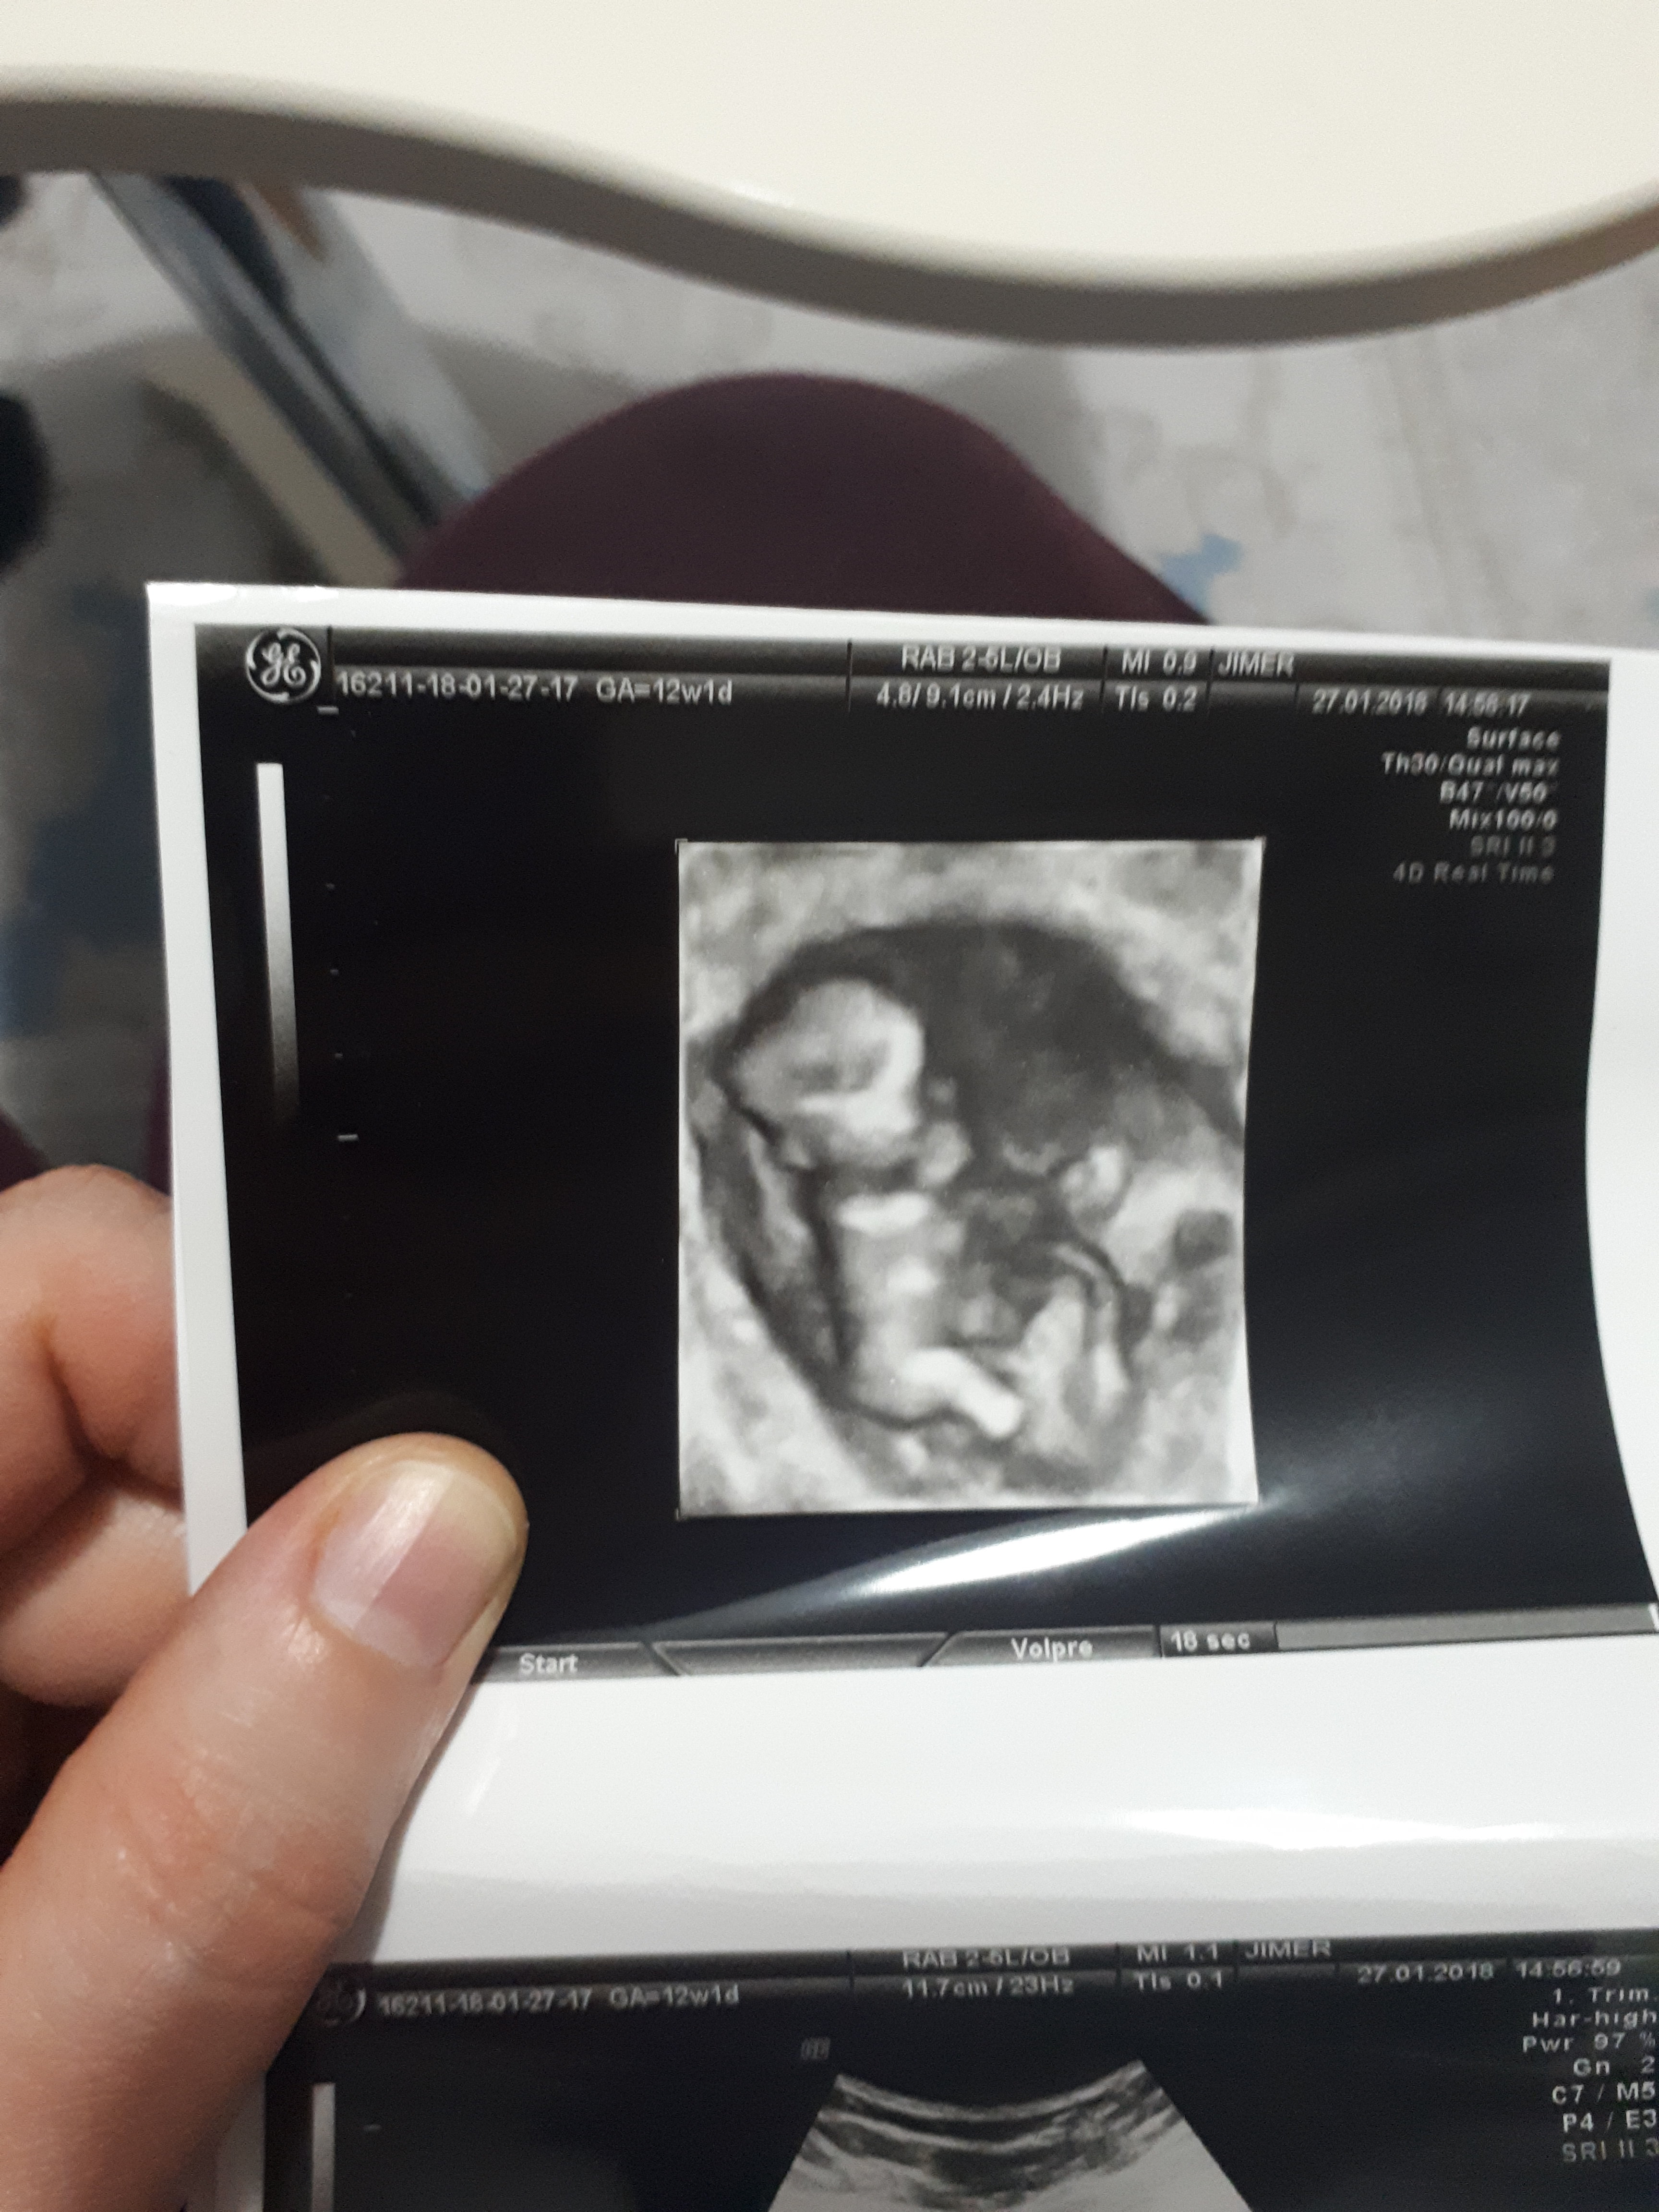

Hadi darısı bana insallah hayırlı olsunbenim nub teorisi doğru çıktı bebeğim kız 🙂

Birde şu görüntü var bunda peki bellimi ama burada 11 haftalikMerhaba canım bebeğinin pozisyonundan dolayı nub çıkıntısı görünmüyorki

Teşekkür ederim🙂Zaten şöyle söylim bu haftalarda yanılma payı çok yüksek bebeğin cinsiyetini yirminci haftalara yakın net olarak öğrenebilirsiniz . Allah hayırlısını versin inş.